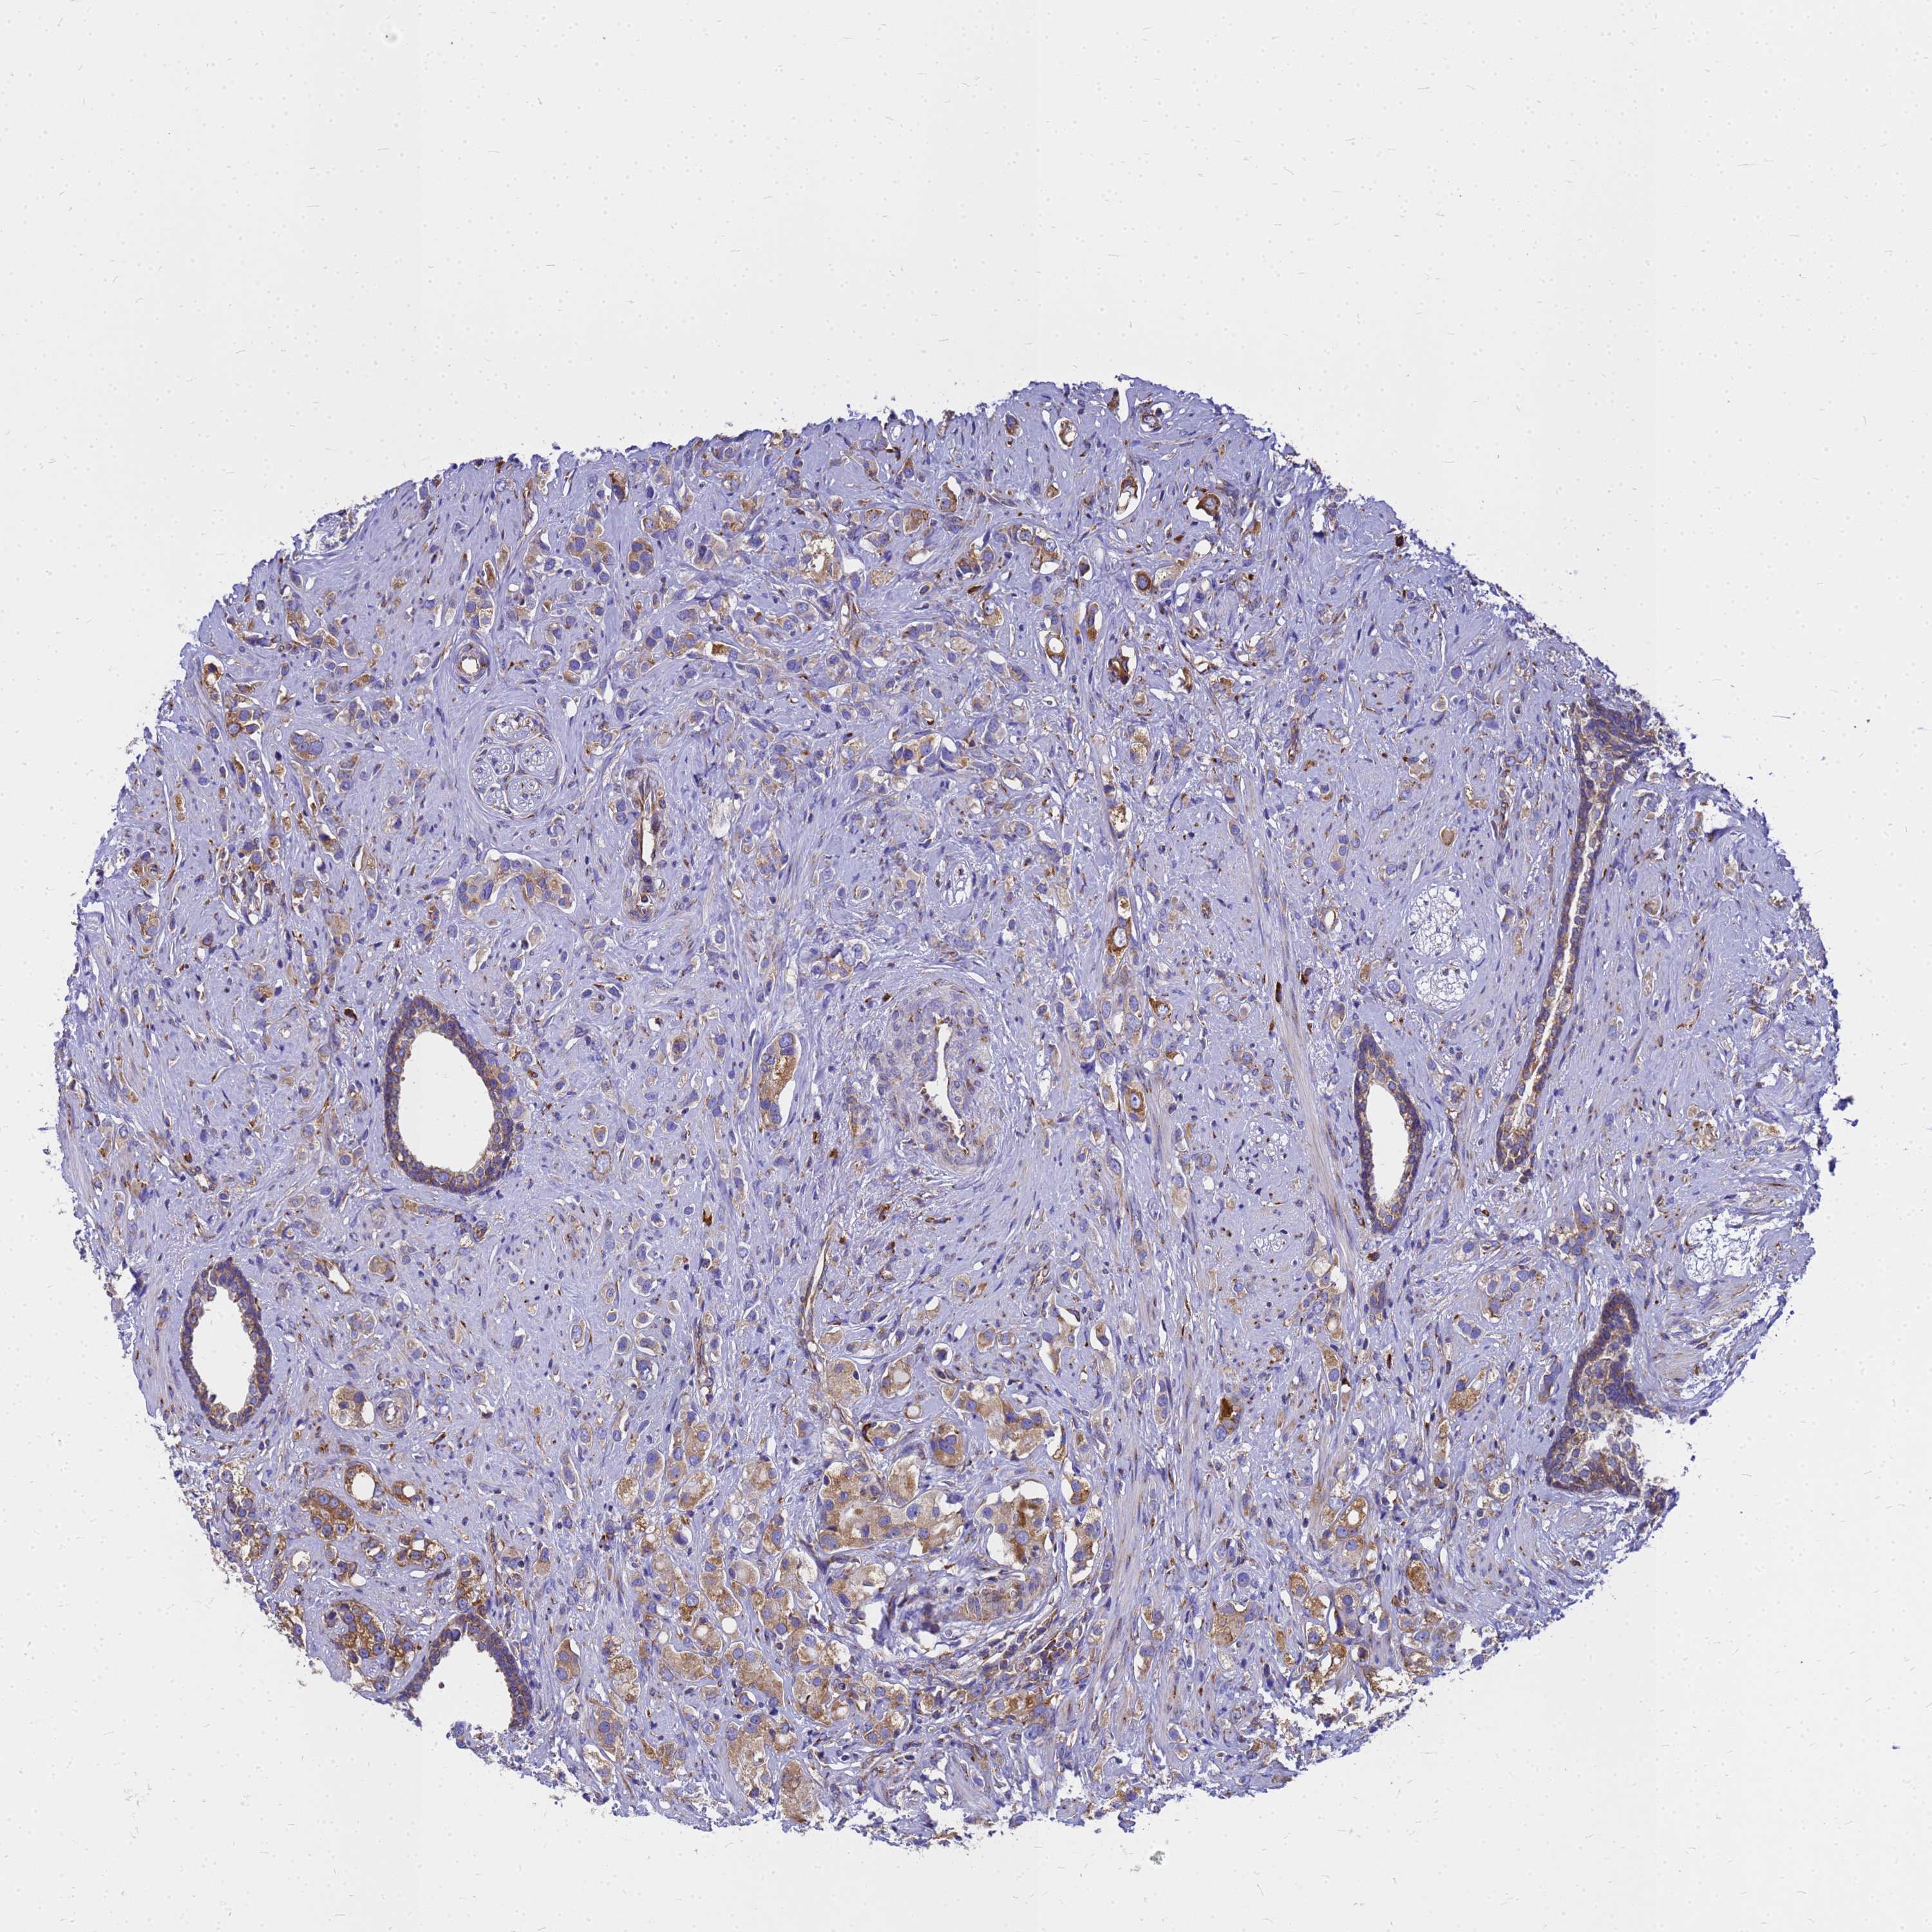

PROSTATE CANCER - Protein expressioni

A mouse-over function shows sample information and annotation data. Click on an image to view it in a full screen mode. Samples can be filtered based on level of antibody staining by selecting one or several of the following categories: high, medium, low and not detected. The assay and annotation is described here.

Note that samples used for immunohistochemistry by the Human Protein Atlas do not correspond to samples in the TCGA dataset.

Antibody stainingi

Antibody staining in the annotated cell types in the current human tissue is reported as not detected, low, medium, or high, based on conventional immunohistochemistry profiling in selected tissues. This score is based on the combination of the staining intensity and fraction of stained cells.

Each image is clickable and will lead to virtual microscopy that enables deeper exploration of all samples and also displays staining intensity scores, fraction scores and subcellular localization as well as patient and tissue information for each sample.

Antibody HPA045101

Staining

High

Medium

Low

Not detected

Intensity

Strong

Moderate

Weak

Negative

Quantity

>75%

75%-25%

<25%

None

Location

Nuclear

Cytoplasmic/membranous

Cytoplasmic/membranous,nuclear

Adenocarcinoma, NOS

Adenocarcinoma, High grade

Adenocarcinoma, Low grade